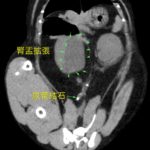

超音波検査で左右の腎盂が著しく拡張していたので、そのまま、無麻酔CT検査を行い左右の尿管結石による左右の腎盂拡張が確定されました。直ちに経皮的腎盂穿刺により、腎後性高窒素症、代謝性アシドーシス、高カリウムの補正を行いました。来院から約36時間で高カリウムが消失し、血液データが改善してきたことから、両側同時にマイクロサージェリーで尿管切開により結石摘除を行いました。術後は結石が閉塞していた影響で尿管炎が顕著になるため、尿管狭窄を予防するために、尿管内に一時的ステント留置を行いました。数週間後に再び麻酔下でステント抜去を行います。また、症例によって腎下方移動尿管膀胱吻合術に移行する場合もあります。徐々に腎数値も良化し、尿も沢山排泄されているようで一安心です。